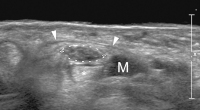

Karpaltunnel

Abbildung 4: Sonographischer Querschnitt durch den Karpaltunnel einer Patientin mit klinischem Verdacht auf ein Karpaltunnelsyndrom. Der Nerv weist eine grenzwertige Querschnittsfläche von 0,11 cm2 auf, allerdings zeigt sich bei Hyperextension ein weit unter das Ligamentum carpi transversum (Pfeilspitzen) reichender Muskelbauch (M).* : normale Beugesehne.